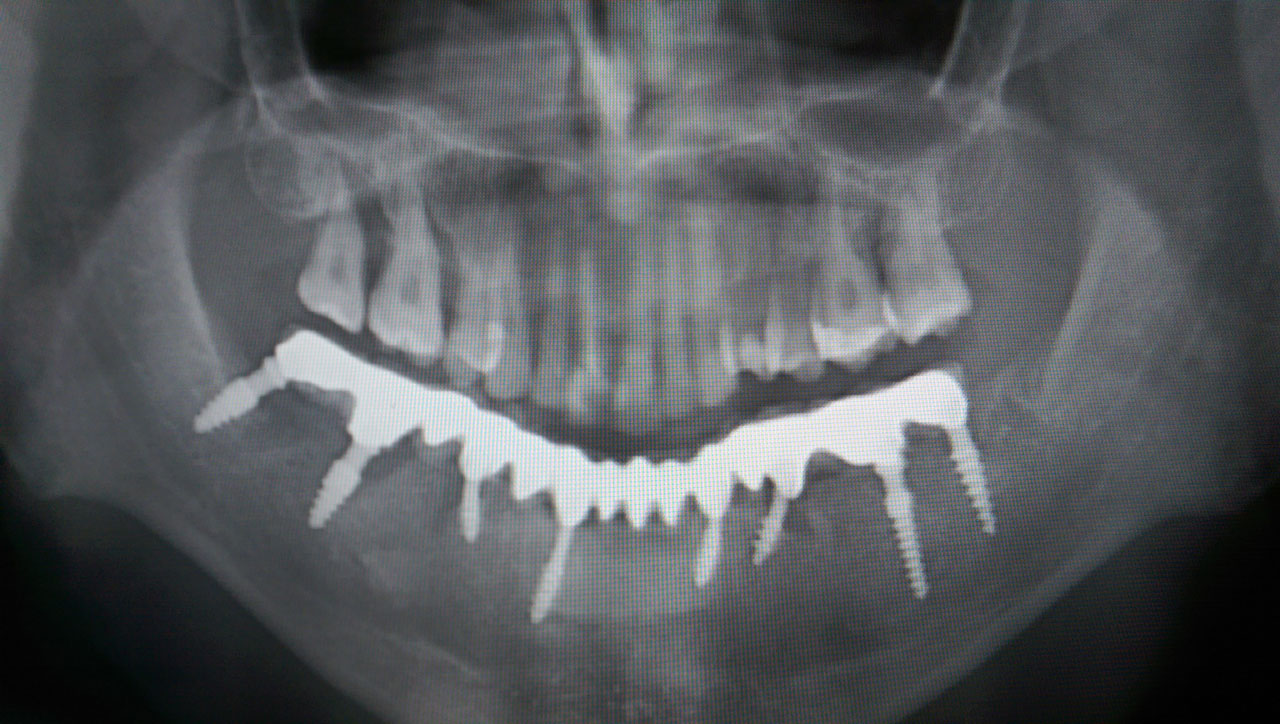

Alsó állcsont teljes rehabilitációja 72 óra alatt, azonnal terhelhető implantátumokkal súlyos paradontitisben szenvedő dohányzó páciens esetében. Az alsó állcsont fogai mind mozogtak az előrehaladott fogágypusztulás miatt.

A fogakat eltávolítottuk, a gyulladt, fertőzött csontot kitakarítottuk, kifertőtlenítettük, majd azonnal implantáltunk.

Svájci, IHDE márkájú, azonnal terhelhető implantátumokat helyzetünk be, és ezekre harmadnapra rögzített, hosszútávú, fémvázas, esztétikus műanyaggal leplezett hidat ragasztottunk be.

Ezt az ideiglenes hidat a sebek gyógyulása miatt használjuk, de tartóssága miatt véglegesként is használható. A legtöbb esetben, ahogy itt is, 6 hónap múlva porcelán hídra cseréljük, a teljes gyógyulás után.